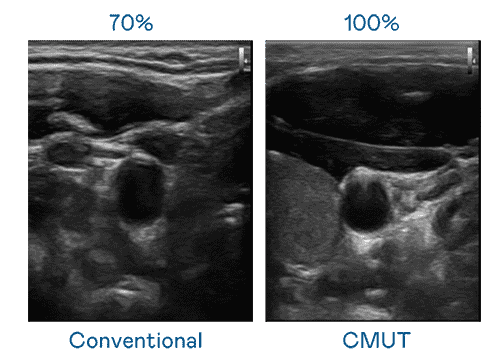

CMUT 技术是一种用电容式微机电元件来产生超音波讯号的技术。。与传统 PZT 压电式技术相比,,,CMUT 频宽增加 30%,,,,更宽频的超音波讯号让影像解析度大幅提升,,是实现高影像品质医疗超音波扫描、、、促进精准医疗发展的关键技术。。。

大频宽带来超清晰影像

超音波影像的解析度高低,,首先取决于探头能发出的讯号频宽。。。EBpay CMUT 可提供高清晰的超音波讯号,,,提供高频宽、、高灵敏度、、、、影像纹理细节更高的超音波影像,,,协助医护人员缩短影像判读时间及利用精准的医疗影像进行诊断。。。。